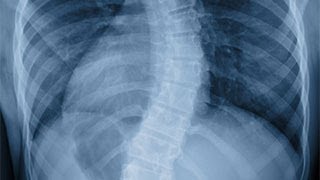

The spine specialists at Akron Children’s are using innovative technologies and techniques to advance care for children and adolescents with abnormal curvature of the spine (scoliosis and kyphosis), as well as other spinal conditions.

Akron Children’s offers both surgical and non-surgical treatment solutions for pediatric and adolescent scoliosis based on your child’s curvature and age. Surgery is typically only performed on children who are going through puberty and are near the end of growth because the procedure can stop the growth of the spine and interfere with chest cavity growth. If your child is too young to undergo scoliosis surgery, we have several treatment options that allow us to prevent or delay the need for surgery.

Idiopathic scoliosis is the most common spinal problem affecting children and teens. The cause is unknown. In other cases, pediatric scoliosis is congenital, meaning the spinal deformity develops before the child is born. Another form is neuromuscular scoliosis, which can occur in children who have medical conditions that affect their ability to control the muscles that support their back and spine.